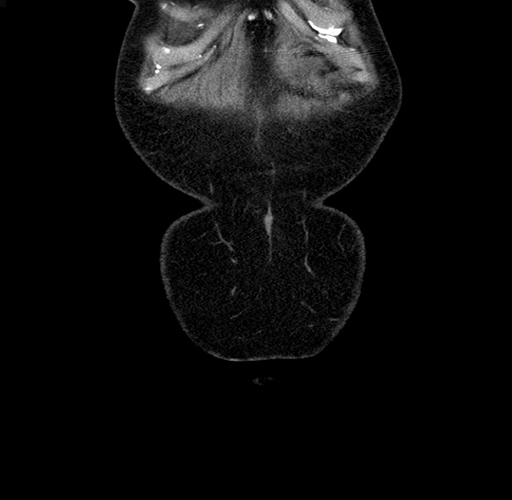

MRI T1